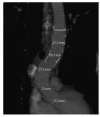

We report two cases of descending thoracic aorta floating thrombus treated with Bolton Relay thoracic free-flow stent graft. The patients had symptoms of lower limb ischemia; they underwent preoperative angiography and CTscan, then we proceeded with endovascular exclusion of the thrombus from the systemic circulation. At 12 months, the graft was still patent in both patients, without any signs of endoleak.